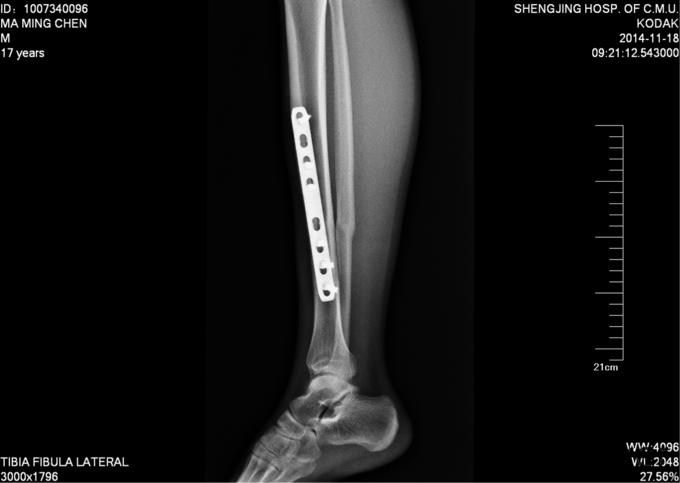

现病史:患者及家属自诉于2013年11月9日下午2点因打篮球摔伤致右小腿疼痛、肿胀,后于2013年11月11号于我院行胫腓骨骨折切开复位内固定术,现内固定物固定已一年半来我科继续治疗。病来无发烧发热,无咳嗽,无其他不良主诉,饮食二便正常,体重近期无明显变化。

患者入病房,右小腿处可见一约10cm瘢痕,瘢痕部无明显压痛,右下肢无轴向叩击痛,无明显肿胀,足趾背伸跖屈肌力5级,足背部及小腿感觉正常,双下肢等长。足背动脉可触及搏动。其余肢体未见异

入院后完善检查,及功能检查后,于全麻下行右胫腓骨骨折术后内固定物出去术,术后第二天换药示切口无红肿渗出,患者自动退院。